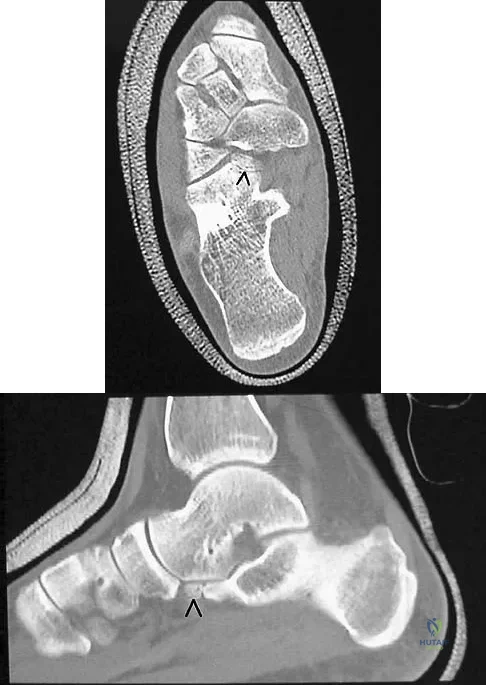

Figures 8a through 8d show the radiographs and CT scans of a 14-year-old girl who has a painful, rigid planovalgus foot. Management consisting of arch supports and anti-inflammatory drugs failed to provide relief. A below-knee walking cast resulted in pain resolution, but she now reports that the pain has recurred. Management should now consist of